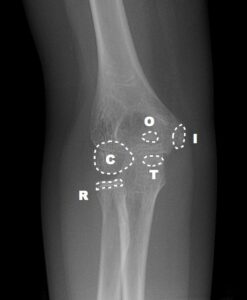

Bu noktaların ortaya çıkma zamanı tahmin edilebilir ancak hastadan hastaya, yaşa, cinsiyete, gelişime göre farklılık gösterebileceği unutulmamalıdır. Karşı taraftaki dirsekle karşılaştırılması patolojik görünüm ya da yapısal farklılığın ayırt edilmesinde yardımcı olur. Bu kemikleşme merkezlerinden ilk ortaya çıkanı Kapitulumdur. Ortaya çıkma sırasına göre “CRITOE” kısaltması kullanılabilir. Kapitulum hariç bu merkezler kızlarda erkeklere göre daha erken görülmektedir.

| KIZ | ERKEK | YAKLAŞIK | |

| C – CAPİTULUM | 1 YAŞ | 1 YAŞ | 1 YAŞ |

| R -RADİUS | 4 YAŞ | 5 YAŞ | 3 YAŞ |

| I – INTERNAL(MEDİAL) EPİKONDİL | 5 YAŞ | 7 YAŞ | 5 YAŞ |

| T – TROCHLEA | 8 YAŞ | 9 YAŞ | 7 YAŞ |

| O – OLECRANON | 8 YAŞ | 10 YAŞ | 9 YAŞ |

| E – EKSTERNAL(LATERAL) EPİKONDİL | 11 YAŞ | 12 YAŞ | 11 YAŞ |

[box type=”info” align=”aligncenter” class=”” width=””]Basitçe ilk merkez olan Kapitulumun 1 yaş civarında ortaya çıktığını diğerlerinin ise yaklaşık 2’şer yıl arayla ortaya çıktığını söyleyebiliriz.[/box]